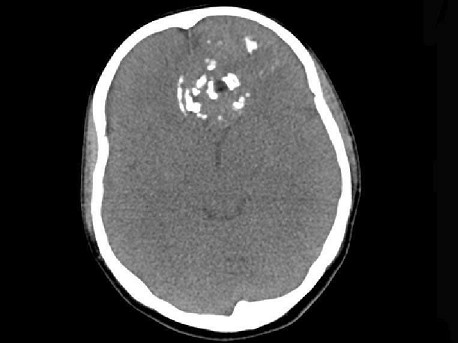

[多选题]男性,28岁,因鼻塞、头痛1年余,鼻窦CT扫描如图所示,请选择正确的描述与结论()A.双侧上颌窦、筛窦、鼻腔及蝶窦内见软组织肿块影B.肿块内密度不均,

A.双侧上颌窦、筛窦、鼻腔及蝶窦内见软组织肿块影

B.肿块内密度不均,有较多致密钙化影

C.窦壁及颅底骨质破坏